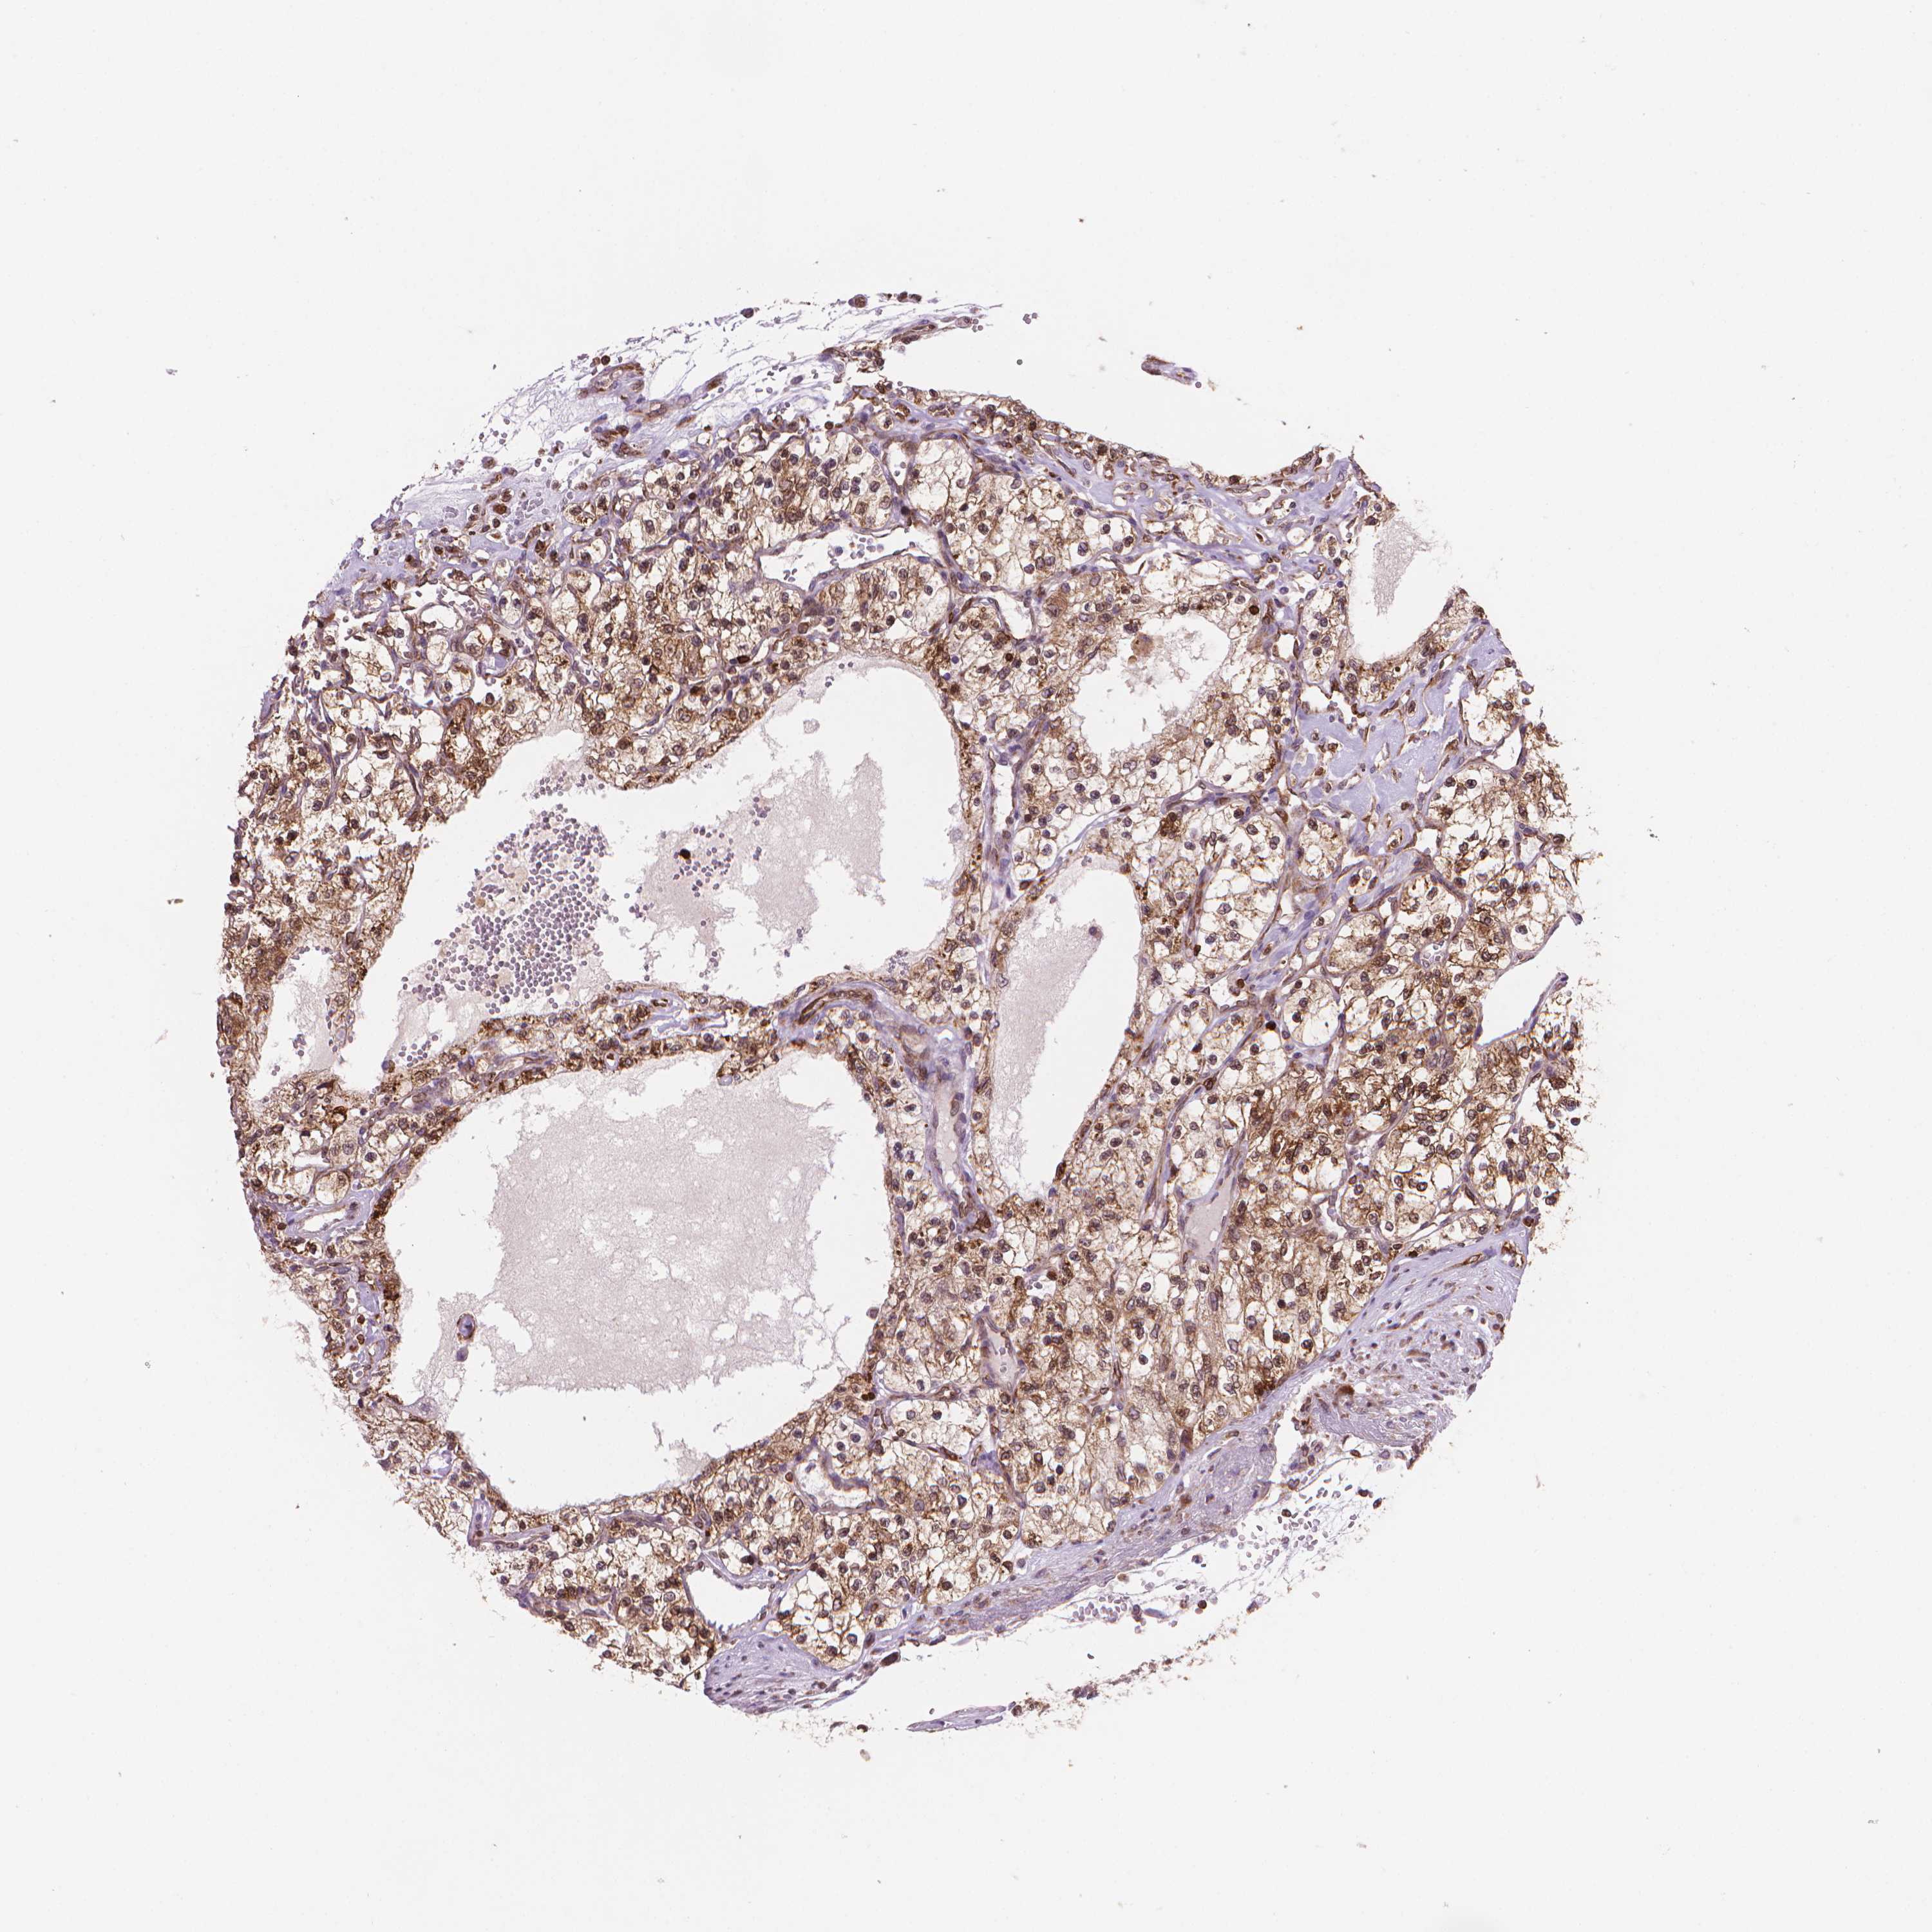

Kidney renal clear cell carcinoma

KIDNEY RENAL CLEAR CELL CARCINOMA (TCGA) - Interactive survival scatter ploti

The Survival Scatter plot shows the clinical status (i.e. dead or alive) for all individuals in the patient cohort, based on the same data that underlies the corresponding Kaplan-Meier plots. Patients that are alive at last time for follow-up are shown in blue and patients who have died during the study are shown in red.

The x-axis shows the expression levels (FPKM) of the investigated gene in the tumor tissue at the time of diagnosis. The y-axis shows the follow-up time after diagnosis (years). Both axes are complimented with kernel density curves demonstrating the data density over the axes. The top density plot shows the expression levels (FPKM) distribution among dead (red) and alive patients (blue). The right density plot shows the data density of the survived years of dead patients with high and low expression levels respectively, stratified using the cutoff indicated by the vertical dashed line through the Survival Scatter plot. This cutoff is automatically defined based on the FPKM cutoff that minimizes the p-score. The cutoff can be changed by dragging the vertical line or by entering a cutoff value in the square labeled "Current cut-off".

Under the Survival Scatter plot the p-score landscape (black curve; left axis) is shown together with dead median separation (red curve; right axis). Dead median separation is the difference in median mRNA expression between patients who have died with high and low expression, respectively. It is calculated as follows: median FPKM expression of dead patients with high expression - median FPKM expression of dead patients with low expression. This is intended to aid the user in visually exploring custom cutoffs and the associated p-scores and dead median separation.

Individual patient data is displayed and can be filtered by clicking on one or more of the category buttons on the top of the page. Categories describing expression level and patient information include: high, low, alive, dead, female, male and tumor stages. The scale of the x-axis can be toggled between linear and log-scale by clicking on the "x log" button. Mouse-over function shows TCGA ID, patient information and mRNA expression (FPKM) for each patient.

& Survival analysisi

Kaplan-Meier plots summarize results from analysis of correlation between mRNA expression level and patient survival. Patients were divided based on level of expression into one of the two groups "low" (under cut off) or "high" (over cut off). X-axis shows time for survival (years) and y-axis shows the probability of survival, where 1.0 corresponds to 100 percent.

BCL2 is validated prognostic, high expression is favorable in Kidney Renal Clear Cell Carcinoma (TCGA)

KIDNEY RENAL CLEAR CELL CARCINOMA (VALIDATION) - Interactive survival scatter ploti

BCL2 is validated prognostic, high expression is favorable in Kidney Renal Clear Cell Carcinoma (validation)

: 13.16